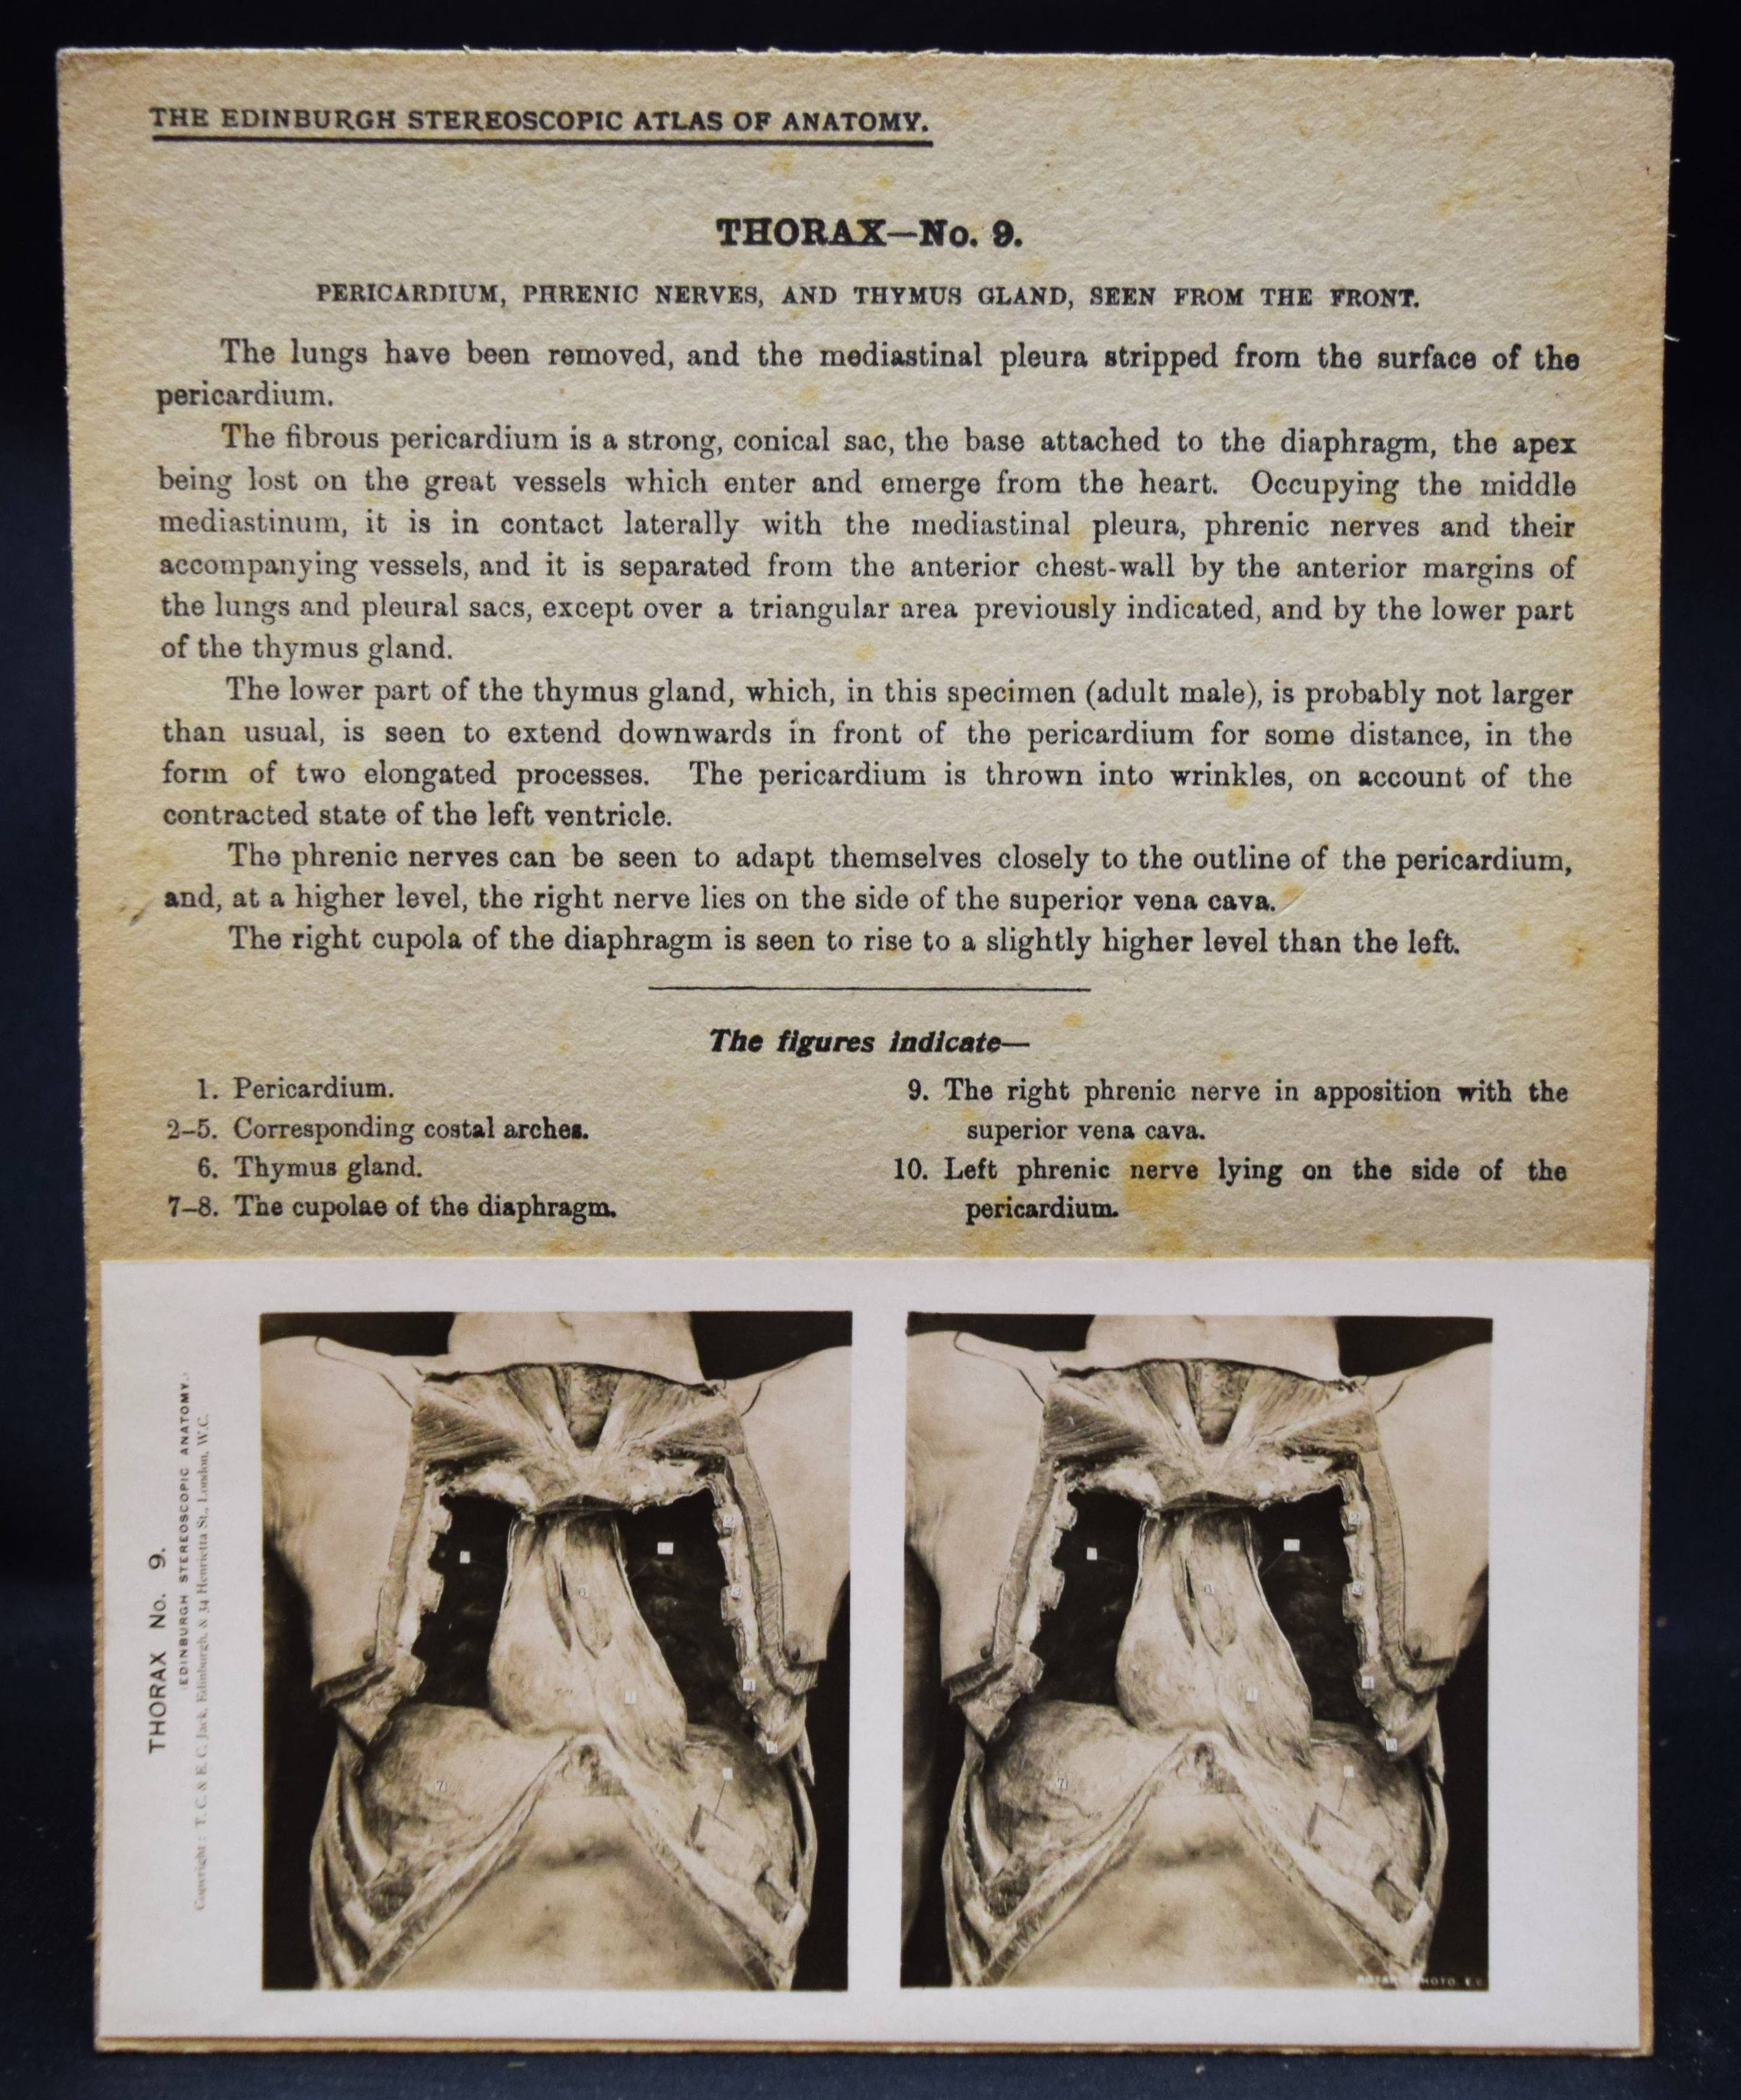

Stereo-Photographie – Waterston, D(avid) and E. Burnet (Ed.). The Edinburgh Stereoscopic Atlas of Anatomy. A New Edition. In five sections with descriptive text. Section 2: Perineum, pelvis, and thorax. Part II (of 5). Edinburgh, T. C. & E. C. Jack o. J. (1905). Gr.-8° (24 x 19 cm.). 50 mont. Orig.-Stereophotographien auf Karton mit beschreibendem Text. Orig.-Papp-Kassette. Vollständiger Teil zur Pneumologie. – Enthält: Abdomen. Pelvis No. 1-12; Pelvis. Female pelvis No. 1-5.; Pelvis. Female perineum No. 1-4; Pelvis. Male perineum No. 1-5; Thorax No. 1-15; Thorax. Lungs No. 1-3; Thorax. Mediastina No. 1-6. – Der schottische Anatom und Chirurg D. Waterston (1871-1942) war seit 1910 Prof. für Anatomie am King’s College in London und seit 1914 an der University of St. Andrews. Waterston hat schon früh die stereoskopische Fotografie eingesetzt um die dreidimensionale Ansicht anatomischer Präparate zu veranschaulichen. – Die Kassette stärker angestaubt, ohne das beil. Textblatt, die Fotografien und Trägerkartons sauber.